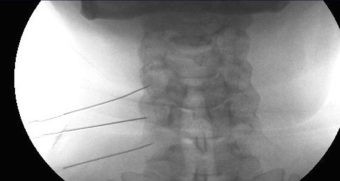

Agujas Colocadas para Bloqueo Transformainal en Cuello